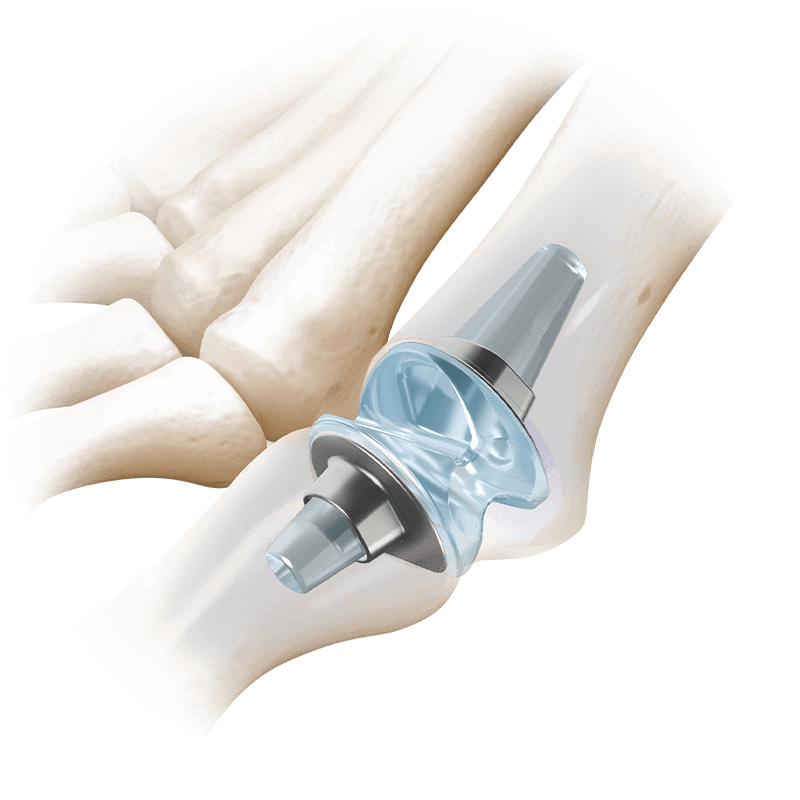

Arthroplasty

RTS® 1st MTP

Medical-grade silicone elastomer with titanium grommets, and a straight-cut technique